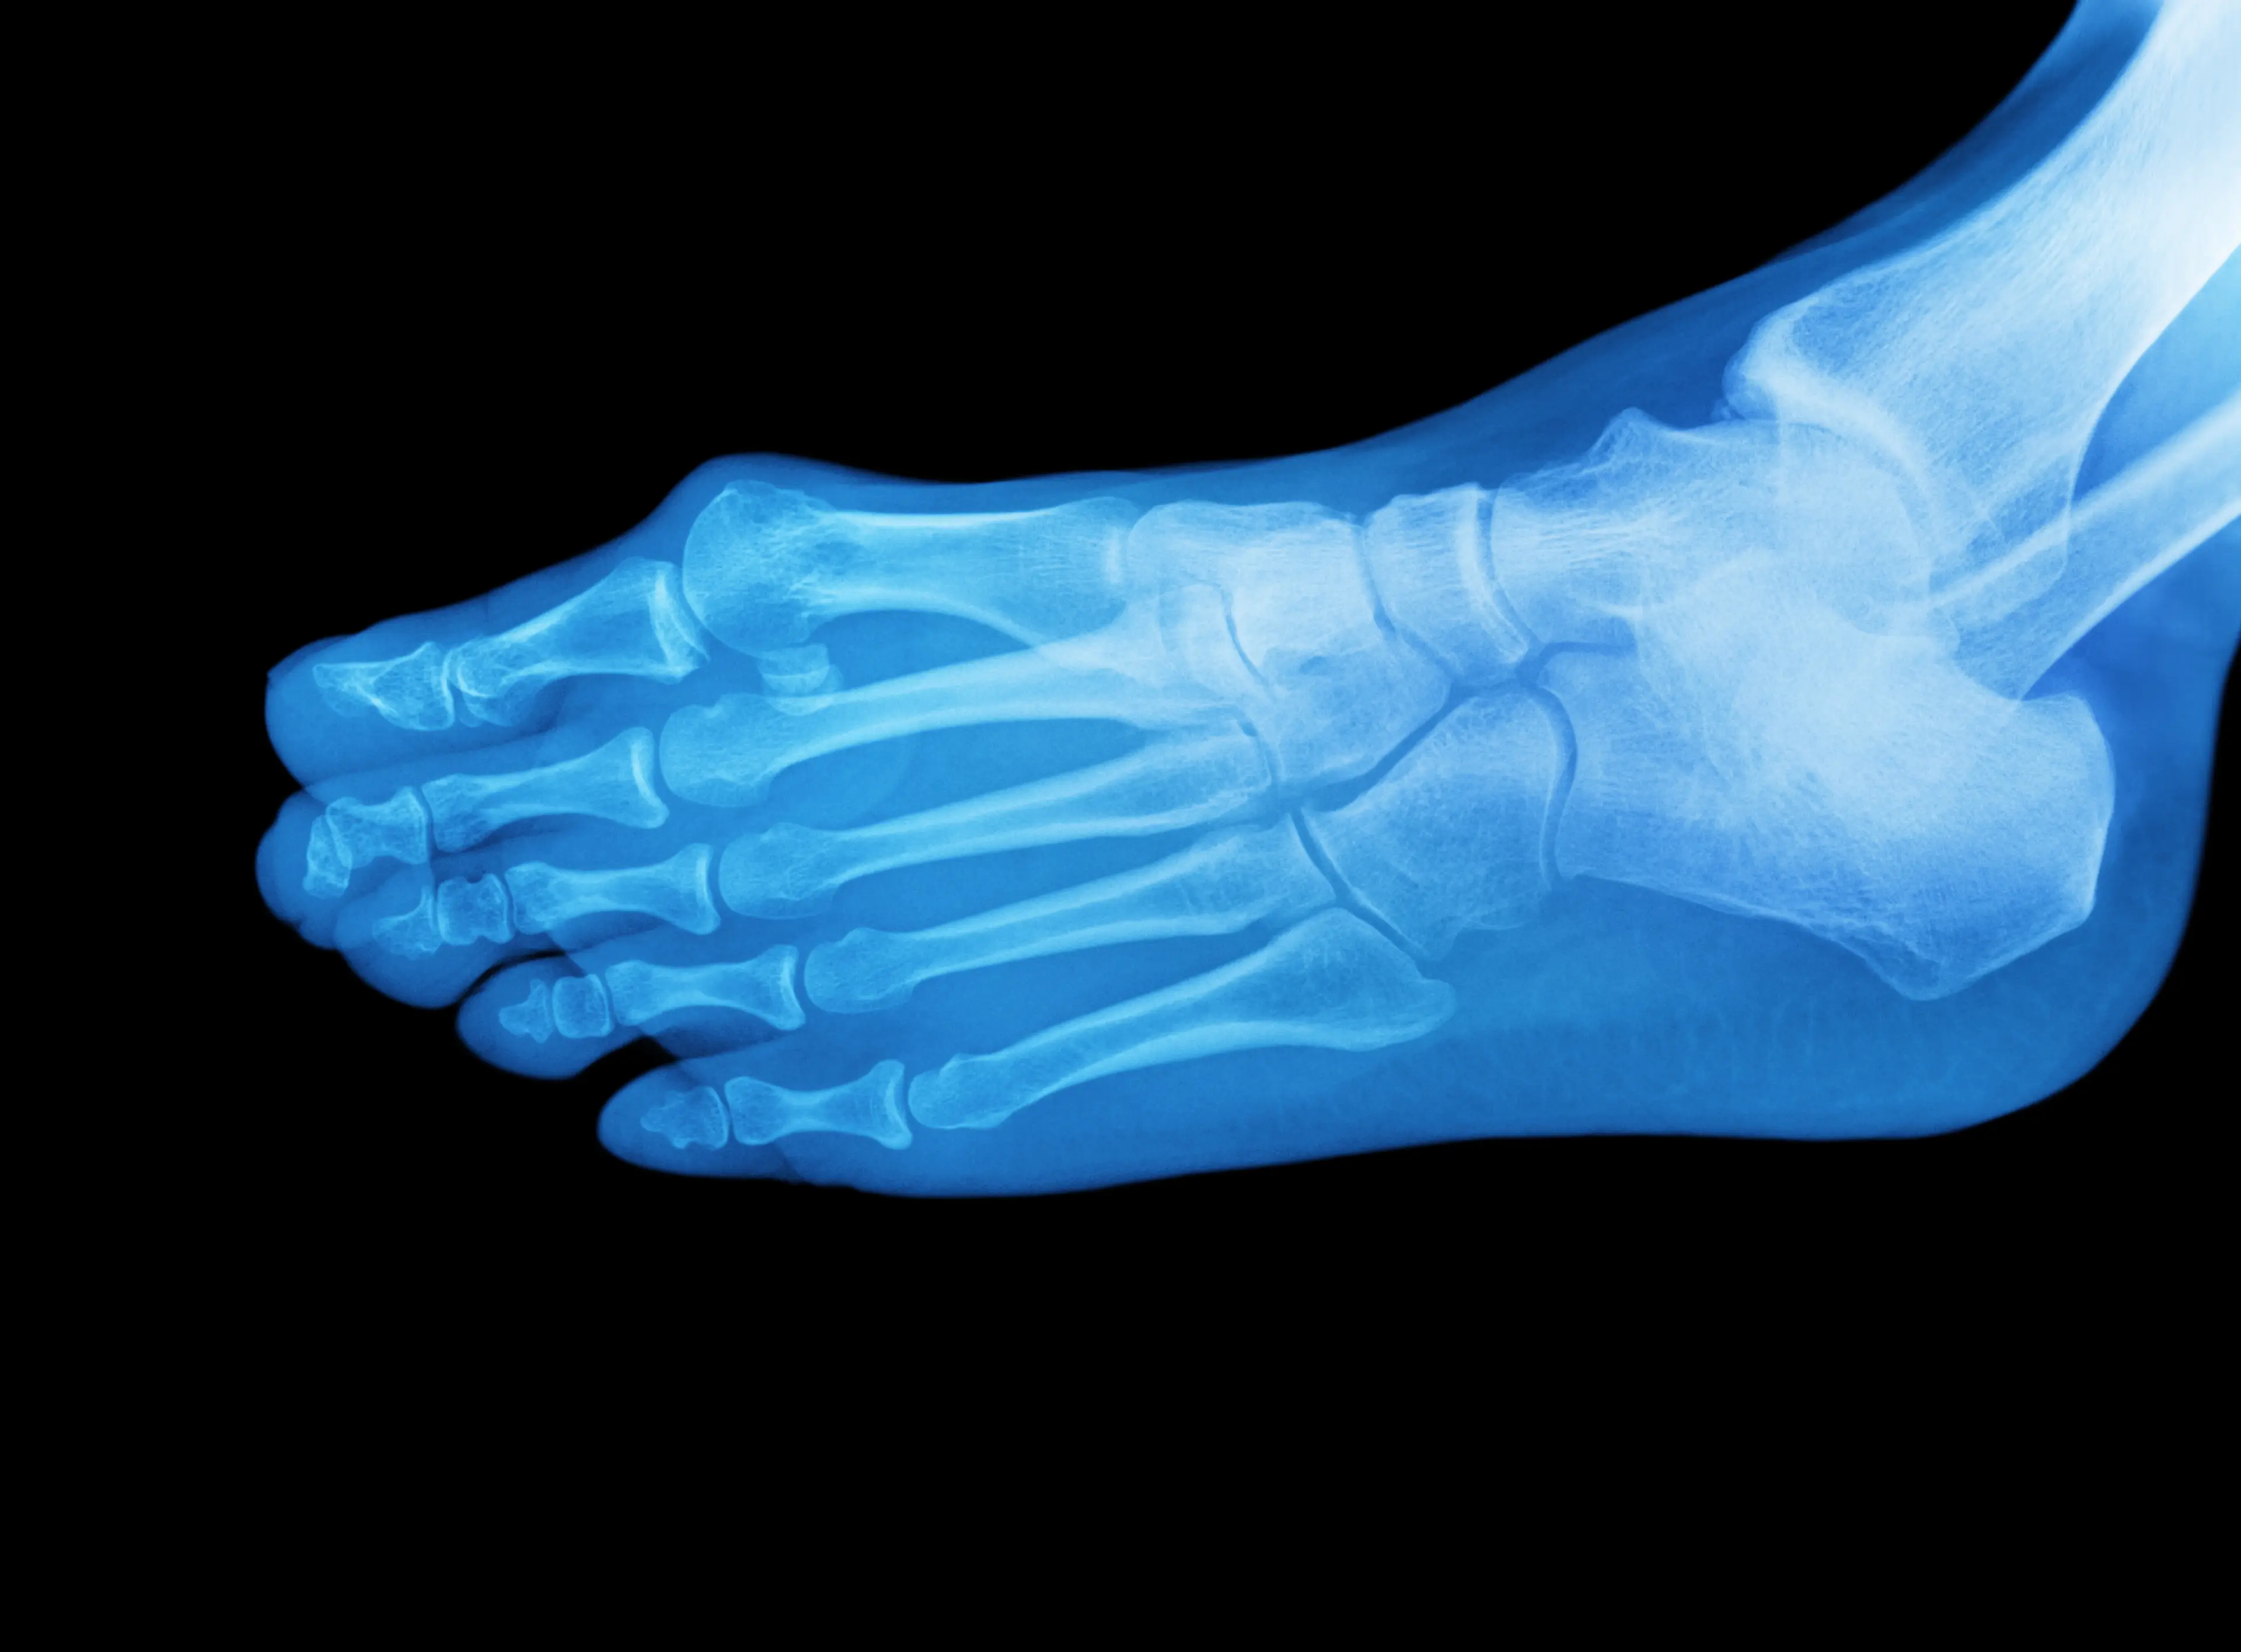

The signs can come from all over the place, but today we're going to make like Quentin Tarantino and focus on the feet.

We can learn a lot about our health from our feet if we know what to look out for and there's three things that you should really be aware of.